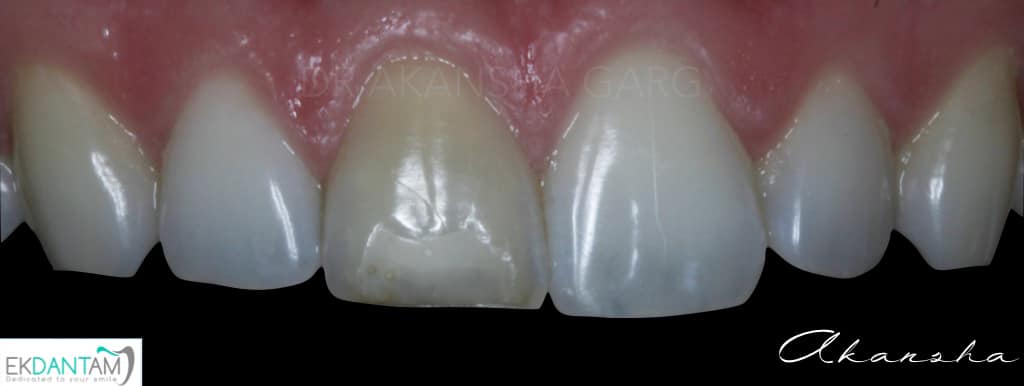

Being gentle to Tooth. It sounds very easy to do subtractive dentistry and grind the tooth and place Crown. The best dentistry is additive dentistry when you save what you have and just replace what’s missing. Case of discoloured tooth due to trauma and Rct years back. Non invasive approach- non vital bleaching followed by composite Incisal edge build up